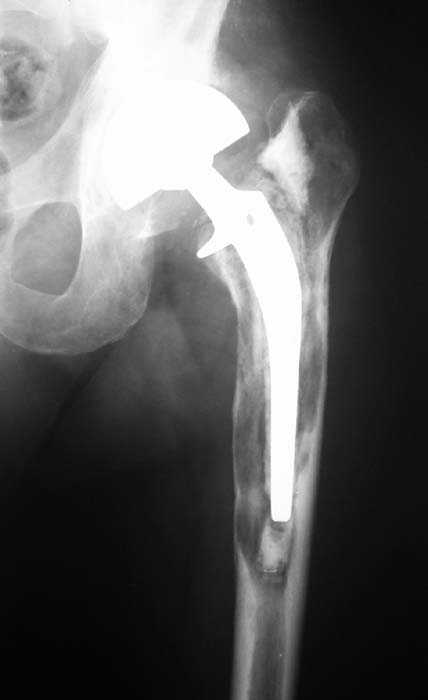

Мужчина, 39 лет.По поводу двустороннего асептического некроза головок бедренных костей последовательно выполнено тотальное эндопроезирование левого (1998 г), затем правого (1999 г) тазобедренных суставов.

26/06/06

С 2001 г отмечает нарастающие боли в левом бедре. Предполагается удаление протеза, удаление цемена из канала бедра, пластика дефекта бедренной кости.

Нет никакого смысла делать операцию в два этапа. С чашкой все понятно - стандартный подход с установкой пресс-фит компонента. На бедре имеет

место перипротезный перелом В3 типа - т.е. перелом вокруг ножки с ее нестабильностью на фоне выраженного остеолиза. Решение - доступ к каналу

через перелом с удалением самой ножки, костного цемента и рубцовых тканей. Установка ножки дистальной фиксации (типа Solution), длину ножки

надо определить по шаблону. Минимальный контакт ножки с интактной костью - 6-8 см. Фрагменты проксмального отдела собираются на ножке

эндопротеза, дефекты костной ткани заполняются чипсами (аллографт) и фиксируются кортикальными аллографтами, уложенными дополнительно по типу

"вязанки хвороста" серкляжом. Мы имеем 8 или 10 подобных наблюдений и результатами довольны.

Абсолютно согласен.Это проверенный путь.Единственное, под Solution надо тщательно удалить цемент из бедра куда встанет дистальная часть ножки.Иначе при установке расколите диафиз бедра.Было поначалу такое у нас.С уважением